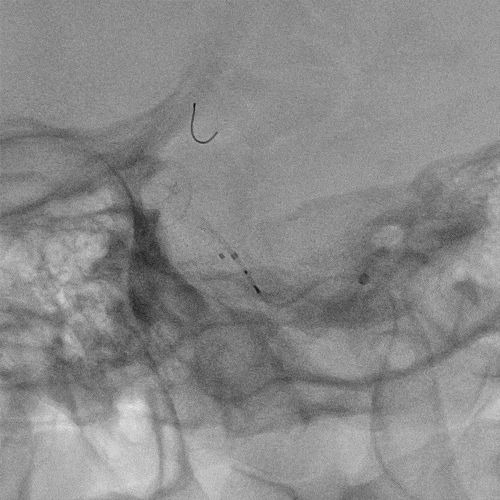

术前BOT实验(+):

患者前后交通动脉代偿不佳,闭塞11分钟患者神志转朦胧,呼之不应。